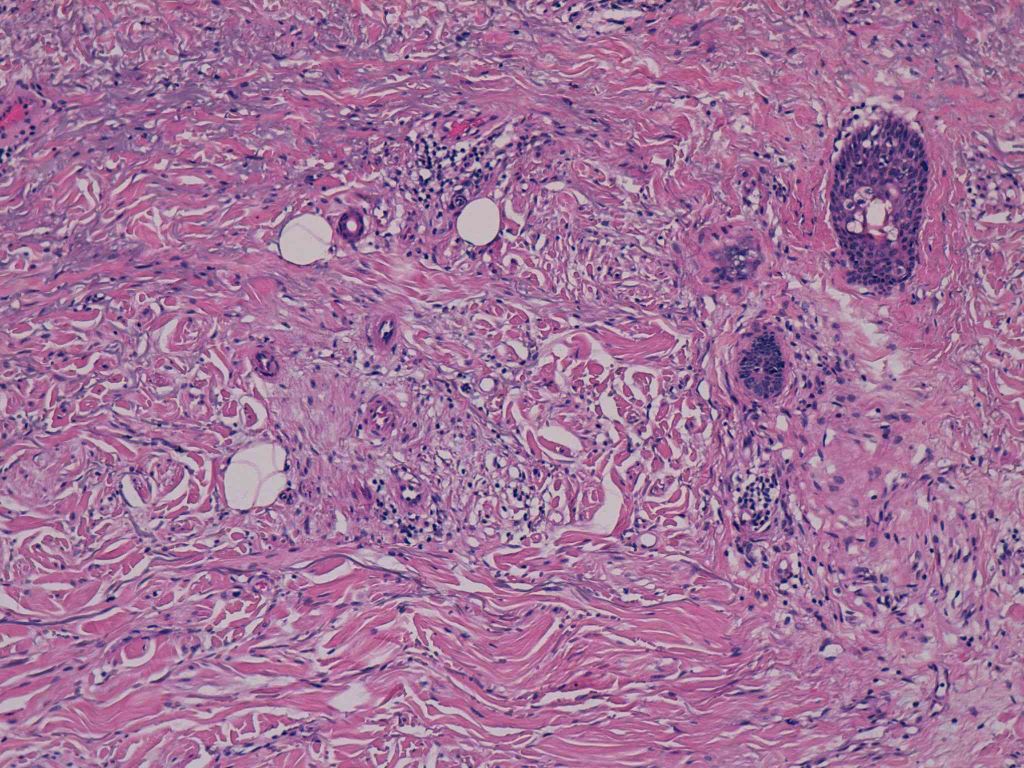

33 -- image_2011y09m11d_17h06m59s.jpg